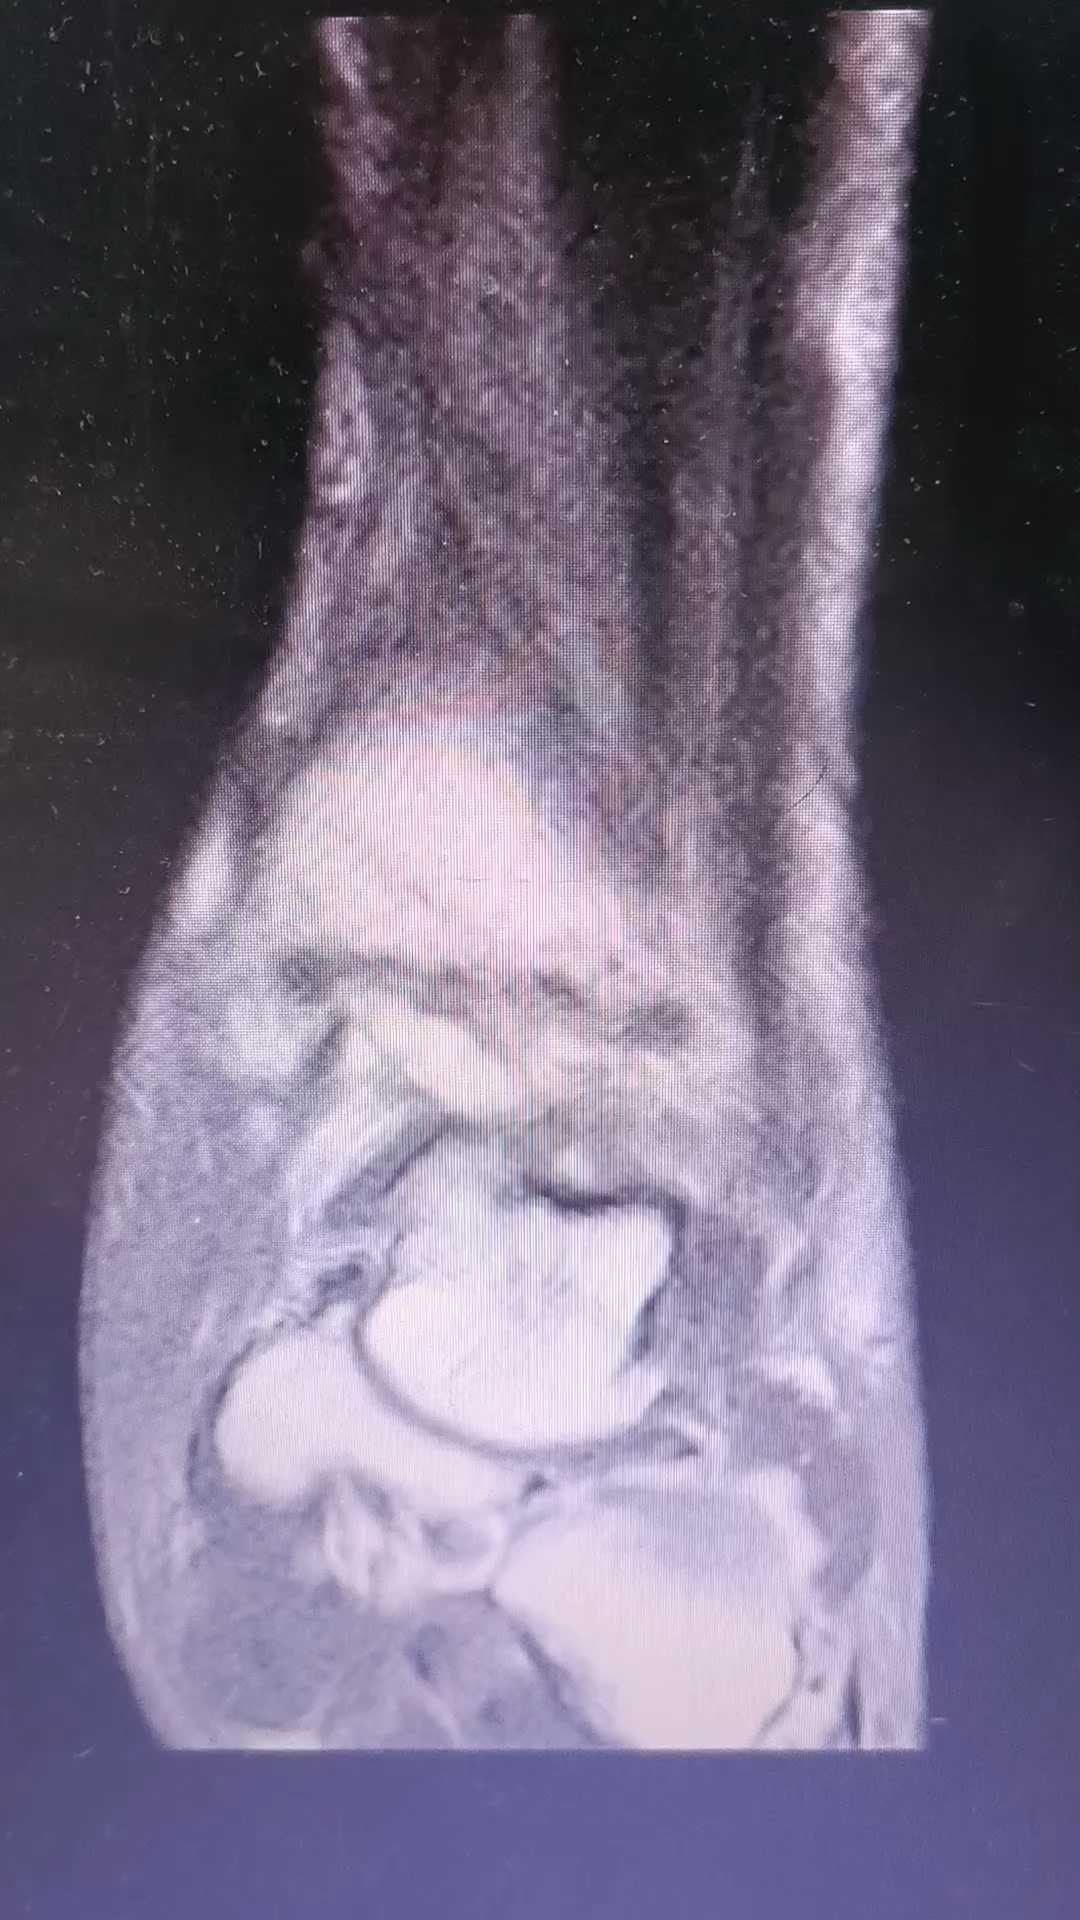

术中腓骨闭复困难,切开辅助穿钉并断端周围植骨。探查见下胫腓前联合韧带损伤,3.5铆钉线穿腓骨前1/3后暂留置。常规3枚空心钉固定后踝。内踝切口探查见三角韧带深层于距骨止点处完全断裂,取出碎骨片,于距骨止点处置入5.0铆钉,一股缝扎三角韧带、另一股穿经胫骨骨道绕腓骨,点式复位钳复位下胫腓关节后,依次结扎各铆钉线,术中透视见距骨复位、内外关节间隙均等,未再置下胫腓螺钉。

术后片